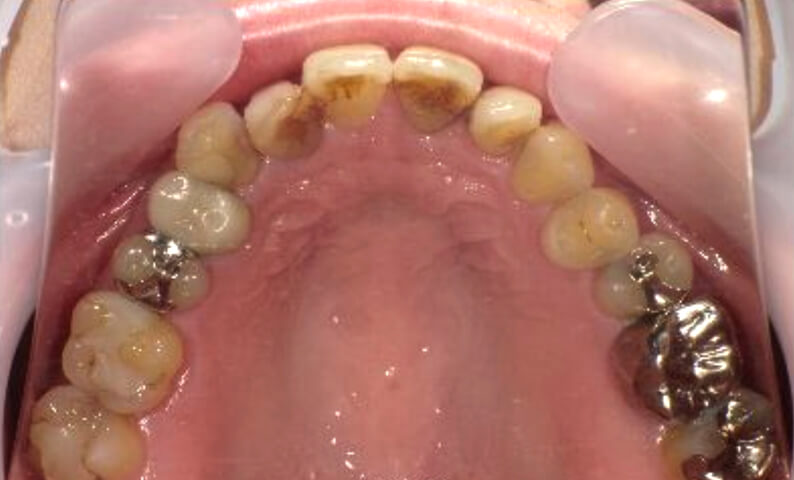

症例_003 下顎だけの部分矯正

治療期間:10ヶ月金額:24万円+税女性前歯のガタガタ下の前歯だけ上顎は補綴治療中

| Before | After |